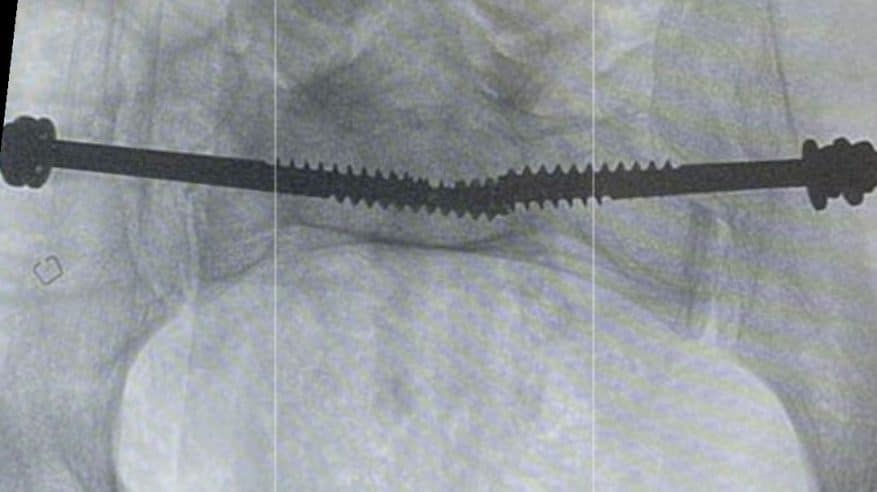

أوضحت “الصحة” أن فريقاً طبياً متخصصاً في قسم العظام في مستشفى الدرعية عضو تجمع الرياض الصحي الثالث تمكن من تثبيت كسر معقد في العظم العجزي في منطقة الحوض للمريض.

وقالت الوزارة إنه تم إرجاع، وتثبيت الخلع في المفصل العجزي الحرقفي لمريض في العقد السادس من العمر عن طريق وضع مسامير طبية باستخدام الأشعة التداخلية.

وأشارت “الصحة” إلى أنه الطريقة المثلى لعلاج مثل هذه الكسور، هي تثبيت الكسر بالطريقة المغلقة لتسهيل تأهيل المريض ومساعدته على التحرك بشكل أسرع، موضحة أن الإجراء يتم عن طريق فتحة في الجلد من 2 إلى 3 سم تحت التخدير العام.